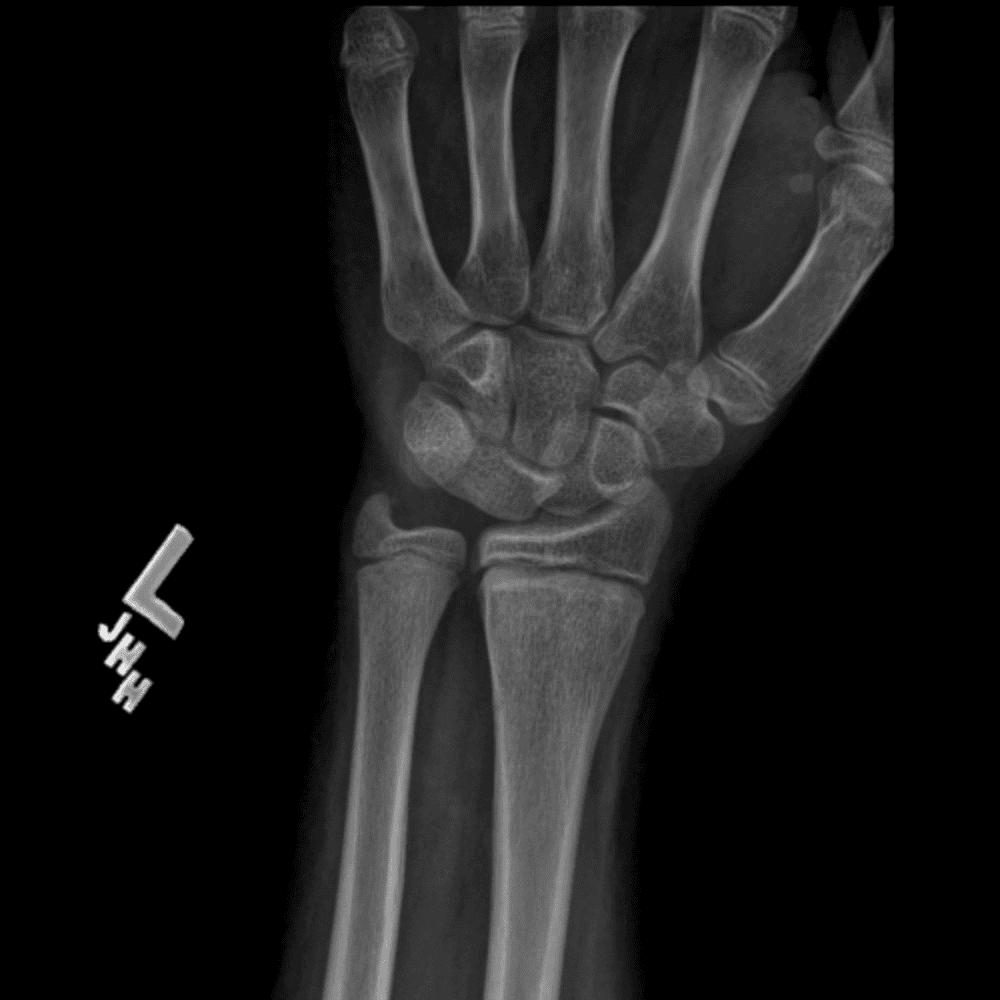

Simulates call by including subtle or difficult cases and some normals.

30 cases